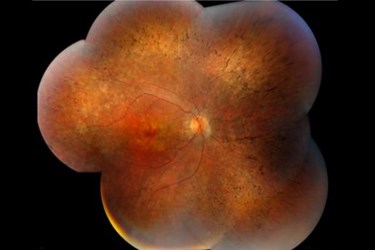

But a new Duke University study says it can link what is in a patient's urine to gene mutations that cause retinitis pigmentosa, or RP, an inherited, degenerative disease that results in severe vision impairment and often blindness. The findings appear online in the Journal of Lipid Research.

Guan's collaborators had previously sequenced the genome of this family and found that the children with RP carry two copies of a mutation at the dehydrodolichol diphosphate synthase (DHDDS) gene, which makes the enzyme that synthesizes organic compounds called dolichols. In humans, dolichol-19, containing 19 isoprene units, is the most abundant species.

The DHDDS mutation, which was found in 2011, is the latest addition to more than 60 gene mutations that have been implicated in RP. This mutation appears to be prevalent in RP patients of the Ashkenazi Jewish origin, and 1 in 322 Ashkenazi carries one copy of the mutation.